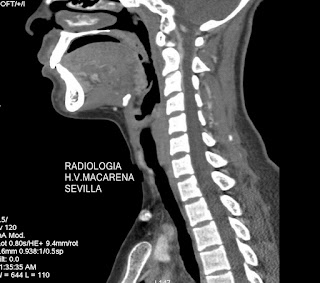

La mayoría se producen en la región de cabeza y cuello, aunque el que se presenta por poco se sale de la norma, ya que se aprecia en la encrucijada entre nuestra amada región y la de los que se dedican al tórax. Se da en grupos de jóvenes, primera y segunda décadas, así que algunos ya no vamos a poder tener este tipo de lesiones, existiendo, como en tantas otras cosas, un predominio femenino.

En nuestro espécimen, se observa, si uno se fija bien, en la matriz calcificada existente lo que hacía que se palpara como una lesión francamente dura.

No he puesto flechas porque supongo que se verá clara la lesión redondita en la encrucijada esternoclavicular ¿no?